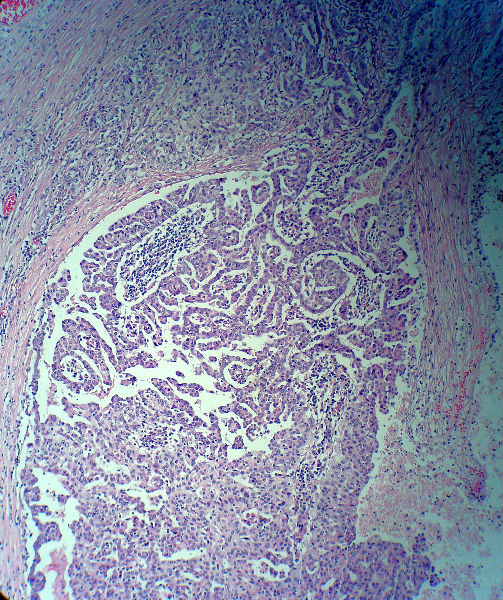

男,82岁,小肠穿孔紧急手术。

大体,小肠一段,长约60厘米,与粘膜面可见三个溃疡型肿物,肠系膜淋巴结肿大。

肿瘤呈巢片状分布,细胞大小相对一致,胞浆丰富,胞核呈细颗粒状,可见小核仁,血管较丰富,考虑神经内分泌肿瘤,加做免疫组化(Ki67、Syn、NSE、CgA、CD56)分级。

没有看见一点小肠粘膜组织,建议重新传图。这些图只能考虑恶性肿瘤。